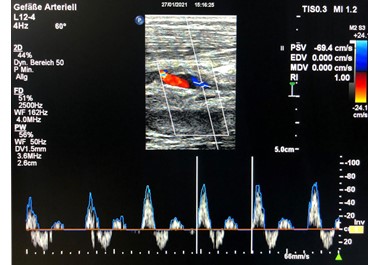

The last follow-up was carried out 16 months after the operation. Duplex sonography shows the vein graft is open with normal flow signals (Figure 3). The peripheral perfusion is normal, the patient is symptom-free.

Fig. 3. Duplex sonograpy of the vein graft 16 months post-op.